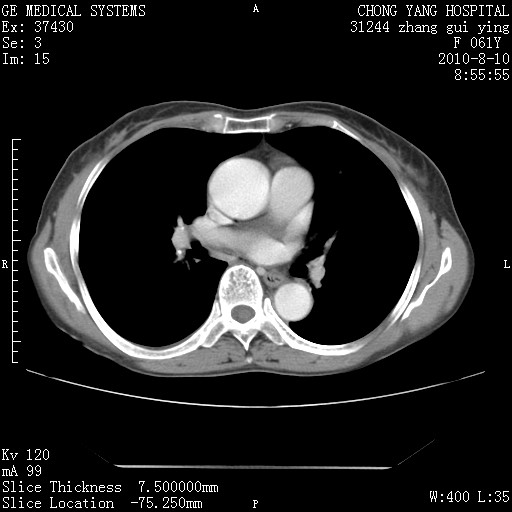

标题: CT28314:F61Y胸部增强,发热咳嗽一周入院,后面的为一周前平

1、支持考虑右侧中央型肺癌伴右肺中叶节段性不张及下叶支气管黏液痰栓    2、左肺上叶舌段感染。

支持3楼意见,还要考虑:纵隔及肺门淋巴结转移、右侧少量胸腔积液。

确切的说:1:右肺下叶中心型肺癌侵及中叶支气管并中叶不张,纵膈淋巴结转移。2:左肺舌叶炎症。3:右侧胸腔少量积液

块影平扫32hu,动静脉期62-70hu.

1:右肺下叶中心型肺癌侵及中叶支气管并中叶不张,纵膈淋巴结转移。2:左肺舌叶炎症。3:右侧胸腔少量积液。支持!